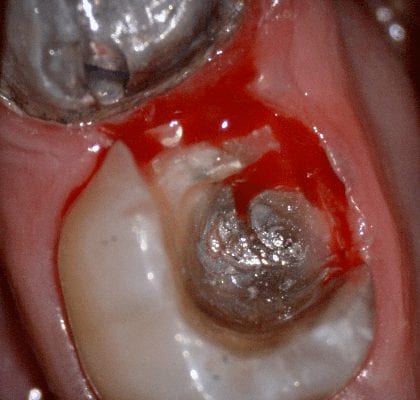

In this video we demonstrate some of the most common problems associated with second molar impressions. Usually the distal margins can be blurred by the presence of hemorrhaging or soft tissue. In this particular case, we use the tip of the camera to displace the tissue and digitall correct an area for better accuracy. The isolite systemisolite systemisolite system does a great job controlling the tongue and the lips and with proper retraction you can image a quadrant in very little time